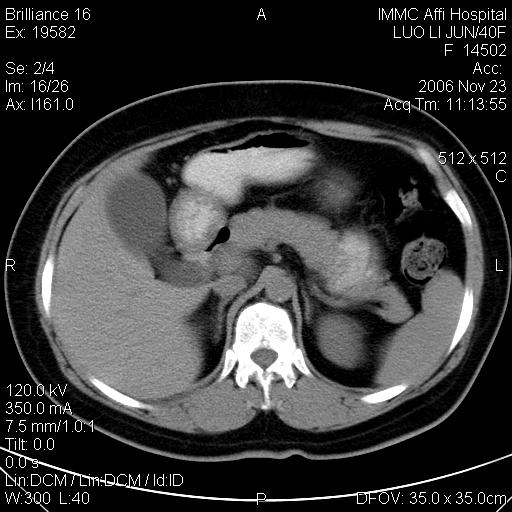

标题: CT5664:我也发一个肝脏的片子大家看看

很典型的肝癌。

典型肝癌

肝癌

速升速降,典型肝癌.

支持-----考虑肝癌----[-从片上看增强早期应该是动脉晚期即门脉早期]

是啊,典型的早出早归!

快进快出典型肝癌.

病灶好圆!可能恶性度不高。

不能除外肝细胞腺瘤吧,还是得结合病史。

很好的片子,可惜增强做的比较失败,a期时间没有把我好,实际到了静脉早期了,否则会更典型。

最终考虑是肝腺瘤